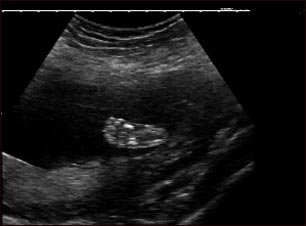

Ultrasonido de un feto normal - pie

Ultrasonido normal a las 19 semanas de gestación. En la parte central de la pantalla se ve claramente el pie derecho, así como los huesos en formación.